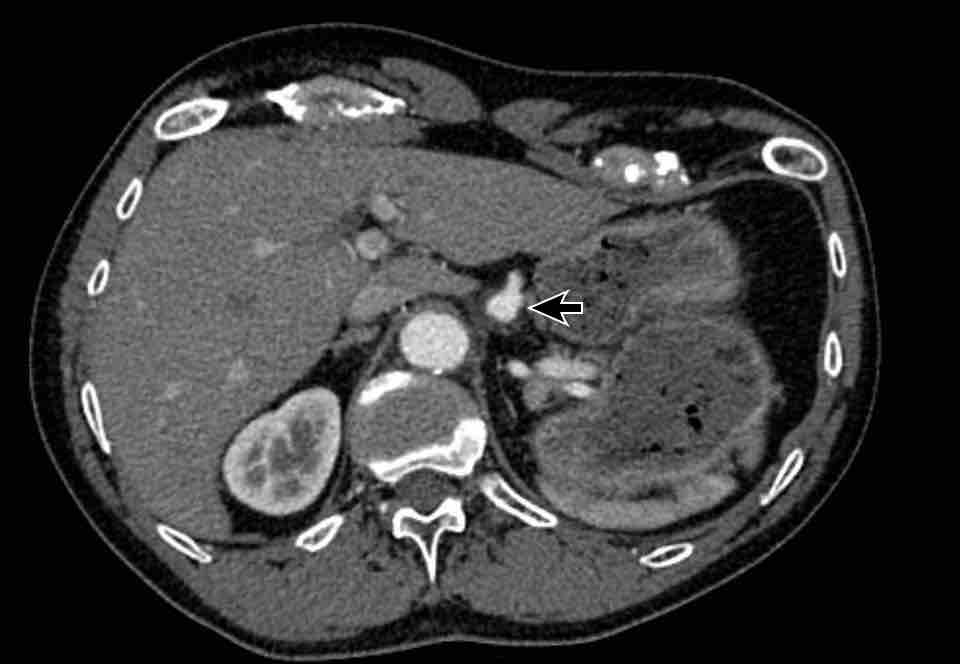

Hình ảnh

Bệnh nhân này được lên kế hoạch cắt thùy trên phải do ung thư phổi và bất thường mạch máu này ban đầu đã bị bỏ sót trên hình ảnh CT.

Những hệ quả trong phẫu thuật của bất thường như vậy nhấn mạnh tầm quan trọng của việc không bỏ sót các biến thể này.